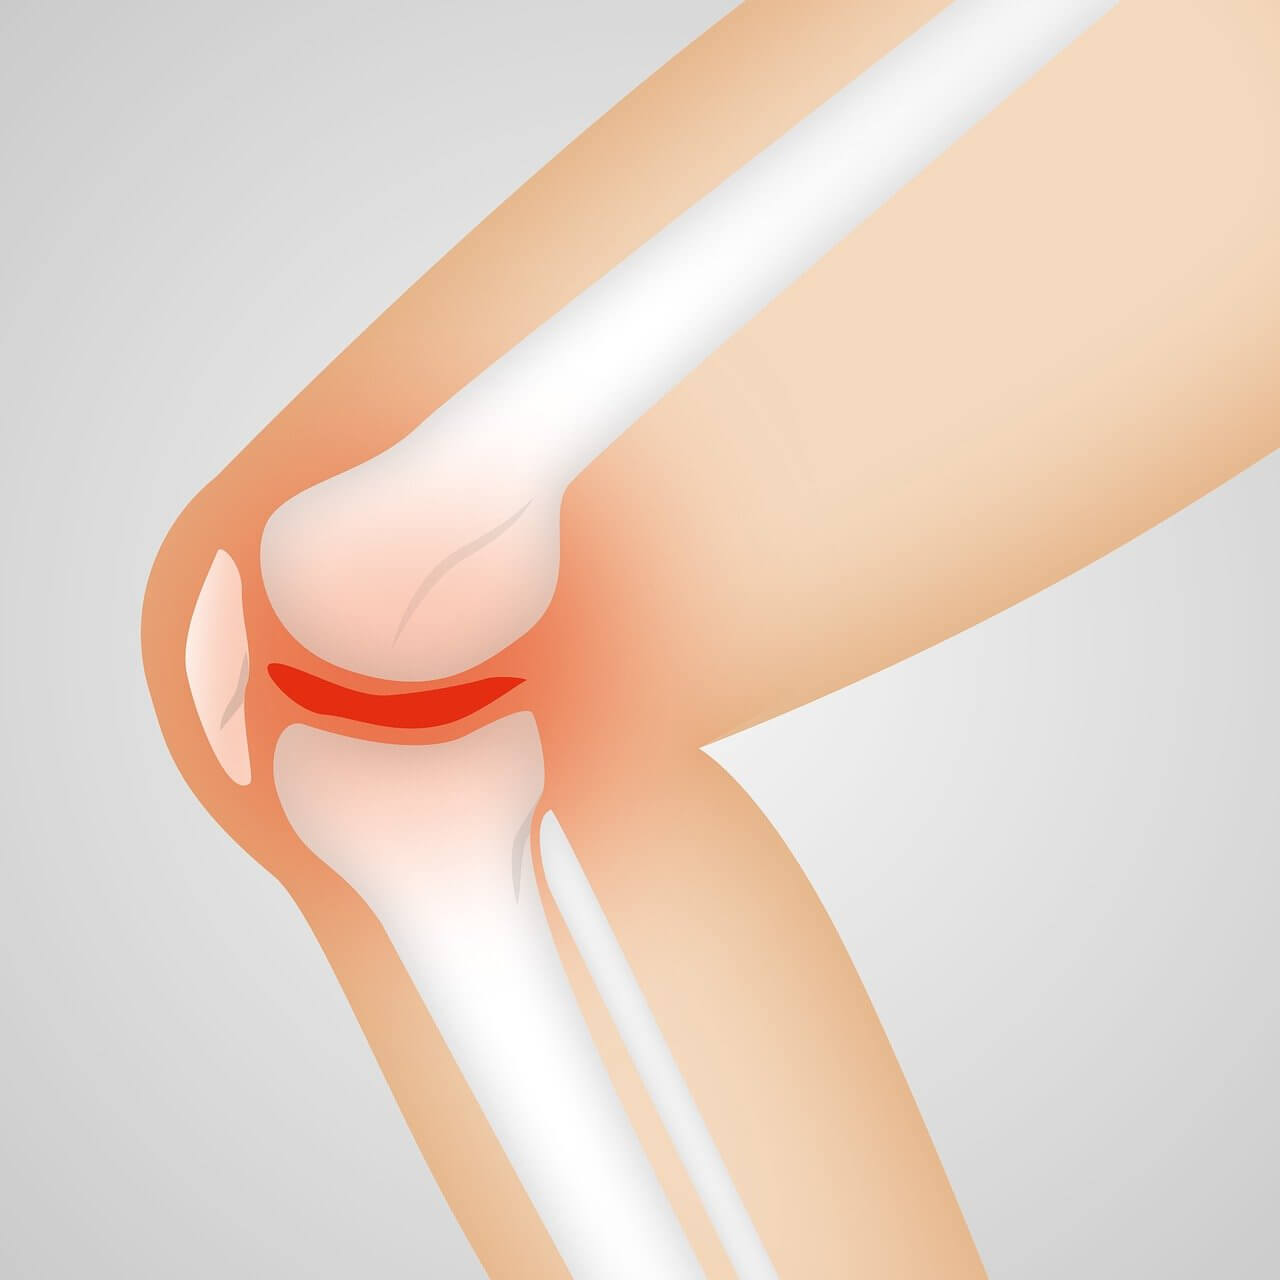

1. 무릎통증 원인, 퇴행성 관절염 (연골이 닳아 생기는 마찰 통증)

퇴행성 관절염은 무릎 관절 사이의 연골이 마모되면서 관절면이 서로 맞닿아 통증과 염증을 유발하는 질환입니다. 나이가 들면서 자연스럽게 발생하기도 하지만, 비만, 무리한 운동, 무릎 부상 등이 무릎통증 원인이 될 수 있습니다. 연골은 신경이 없어 아프지 않지만, 마모되면서 주변 뼈와 조직에 염증을 일으켜 무릎통증이 나타나는 것입니다.